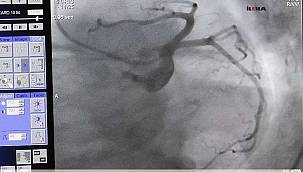

Aşırı stres kalp çarpıntısını tetikliyor!